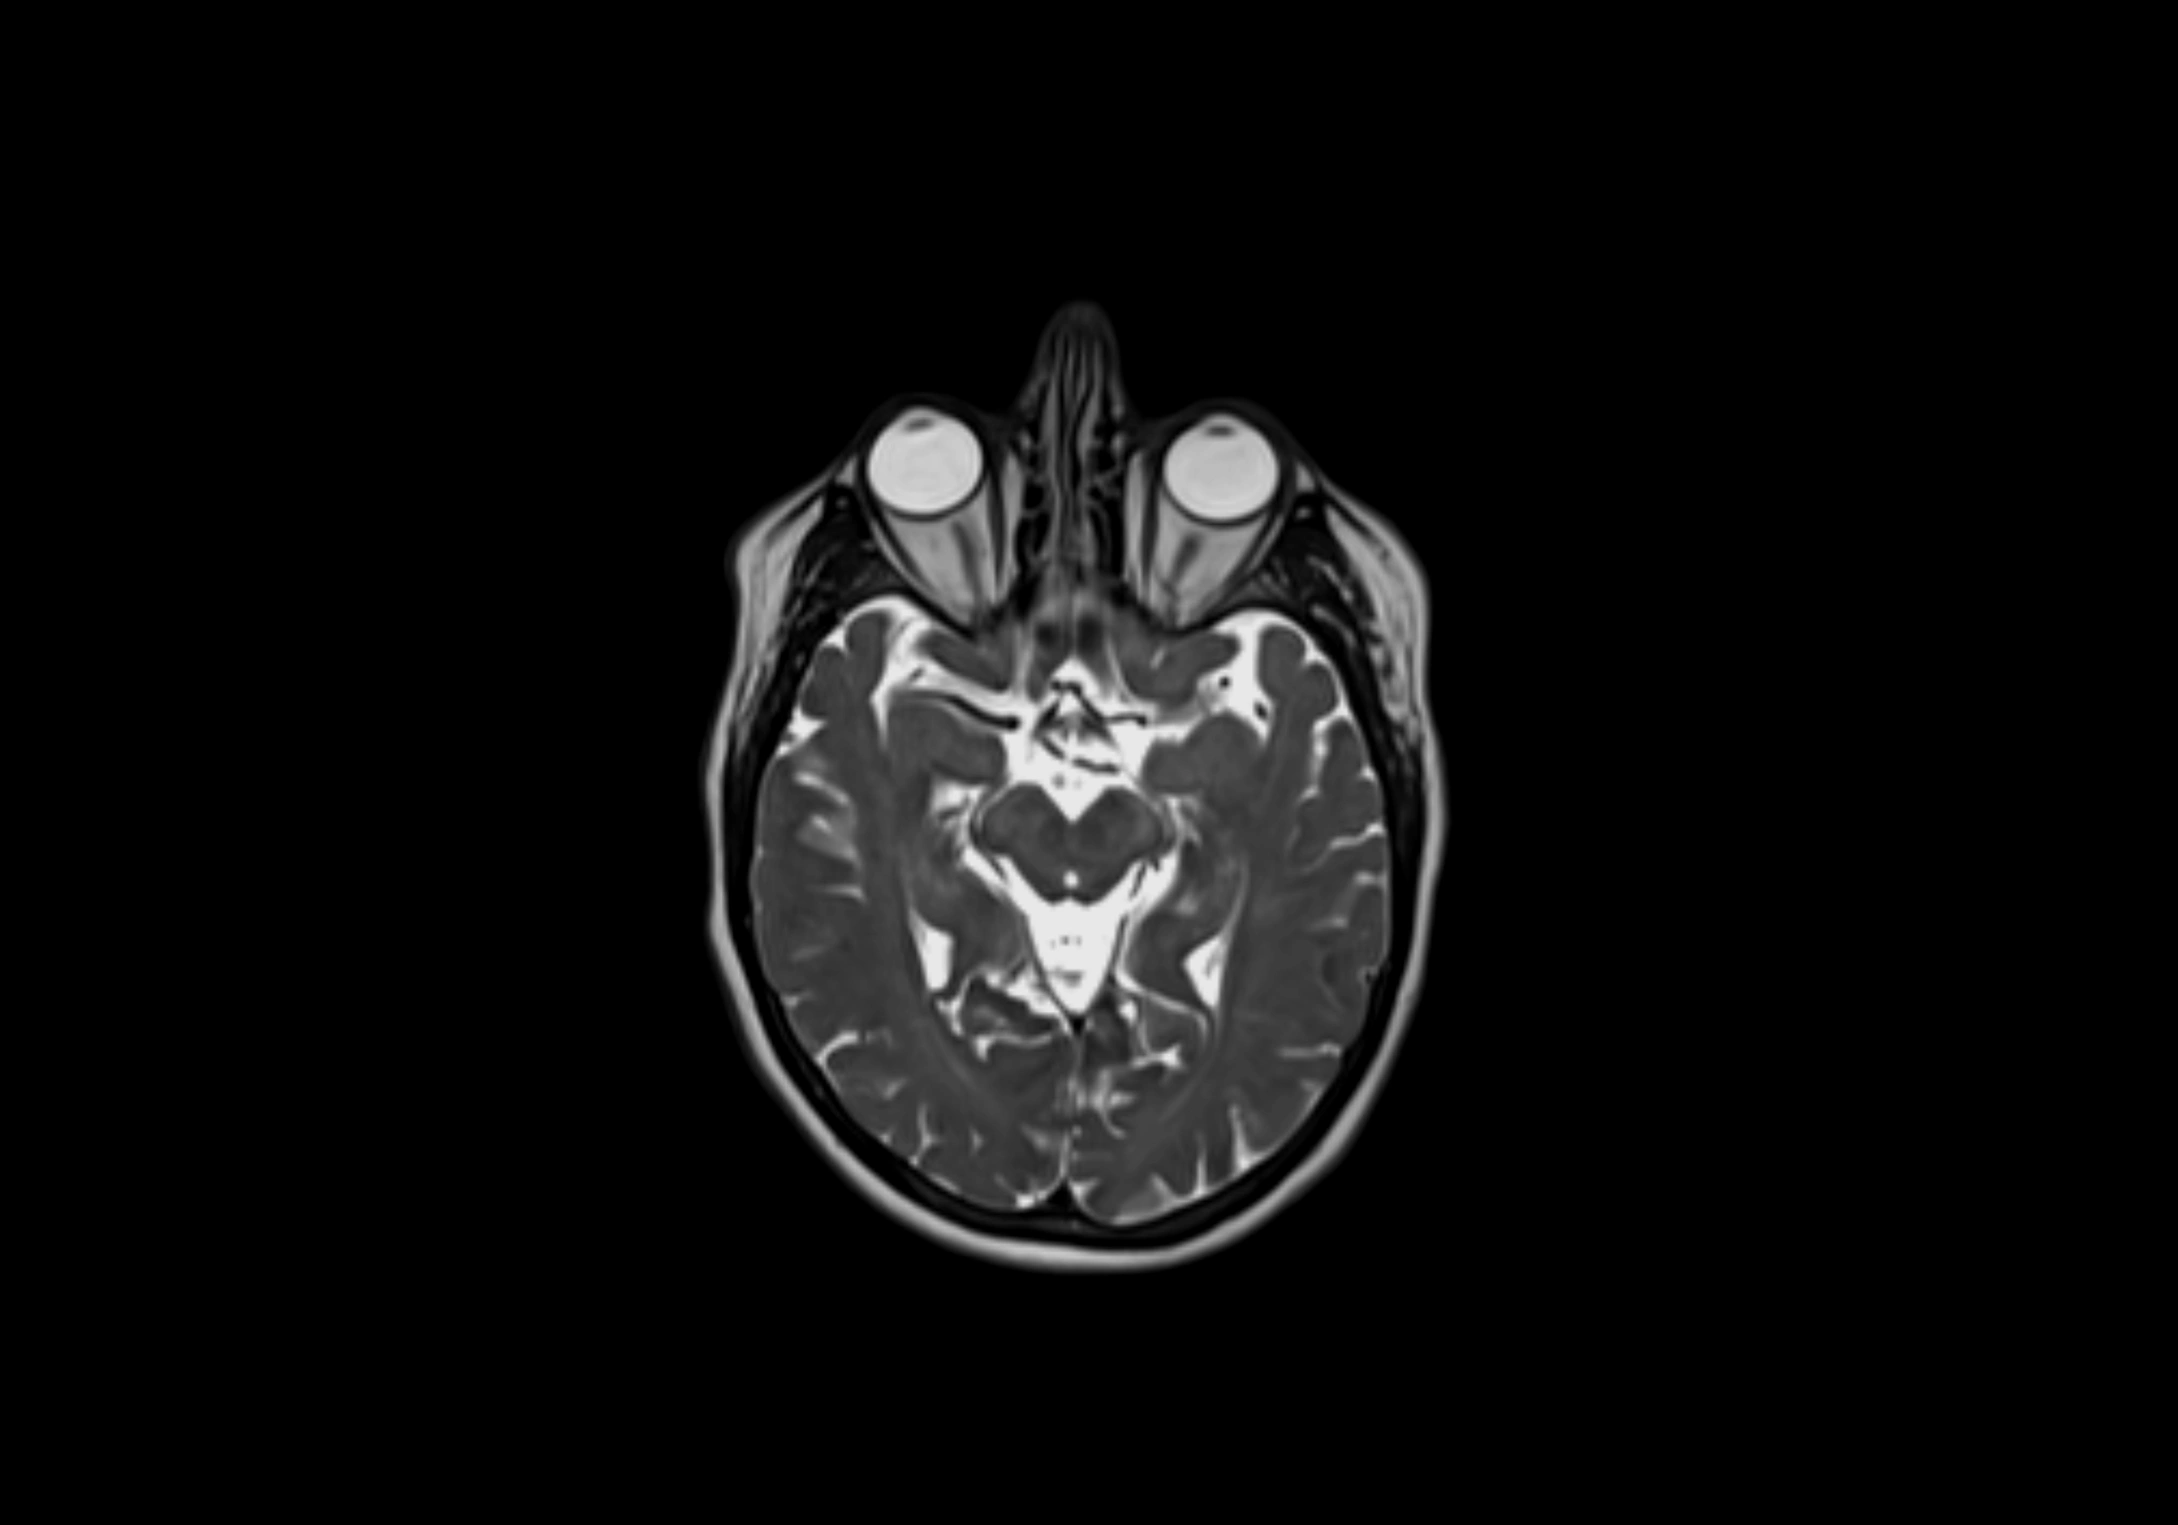

MRI Appearance

T2-weighted images:

• Nodes show intermediate signal, with surrounding fat bright

• Useful for detecting edema, inflammation, or infiltration

• Fatty hilum may appear slightly hyperintense relative to cortex

MRI images